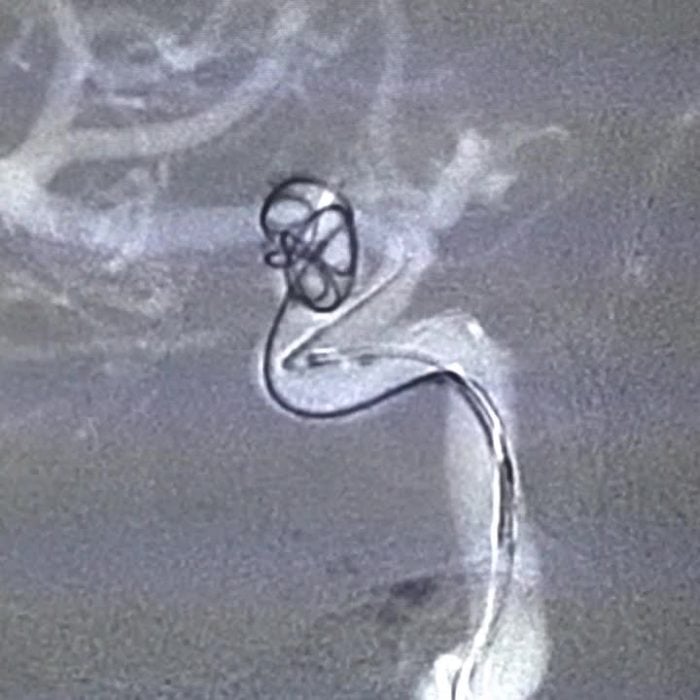

- Coiling Aneurysm: During this minimally invasive procedure, a catheter is inserted into the affected blood vessel, and tiny platinum coils are placed in the aneurysm to promote blood clotting and prevent rupture.

- Stent-Assisted Coiling: In certain cases, a stent may be used to support the coiling procedure, ensuring the coils remain in place and reduce the risk of recurrence.